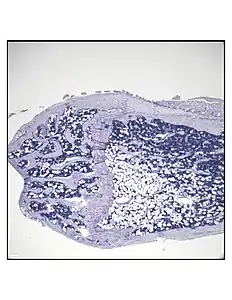

Representative distal femur histologic section of a 16-week-old healthy C57BL/6 mouse demonstrating a typical quantity of marrow adipocytes.

Representative distal femur histologic section of a 16-week-old C57BL/6 mouse after 6 weeks of calorie restriction demonstrating an increased quantity of marrow adipocytes.